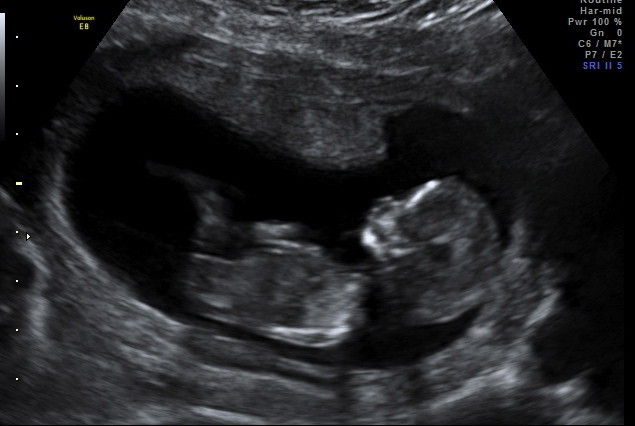

Hi everyone, could you take a guess from this nub shot? It was taken at 12 w 4 d officially, but the baby measured in at 13 w 1 d.

Thank you! :flowerz:Attachment 908Attachment 909